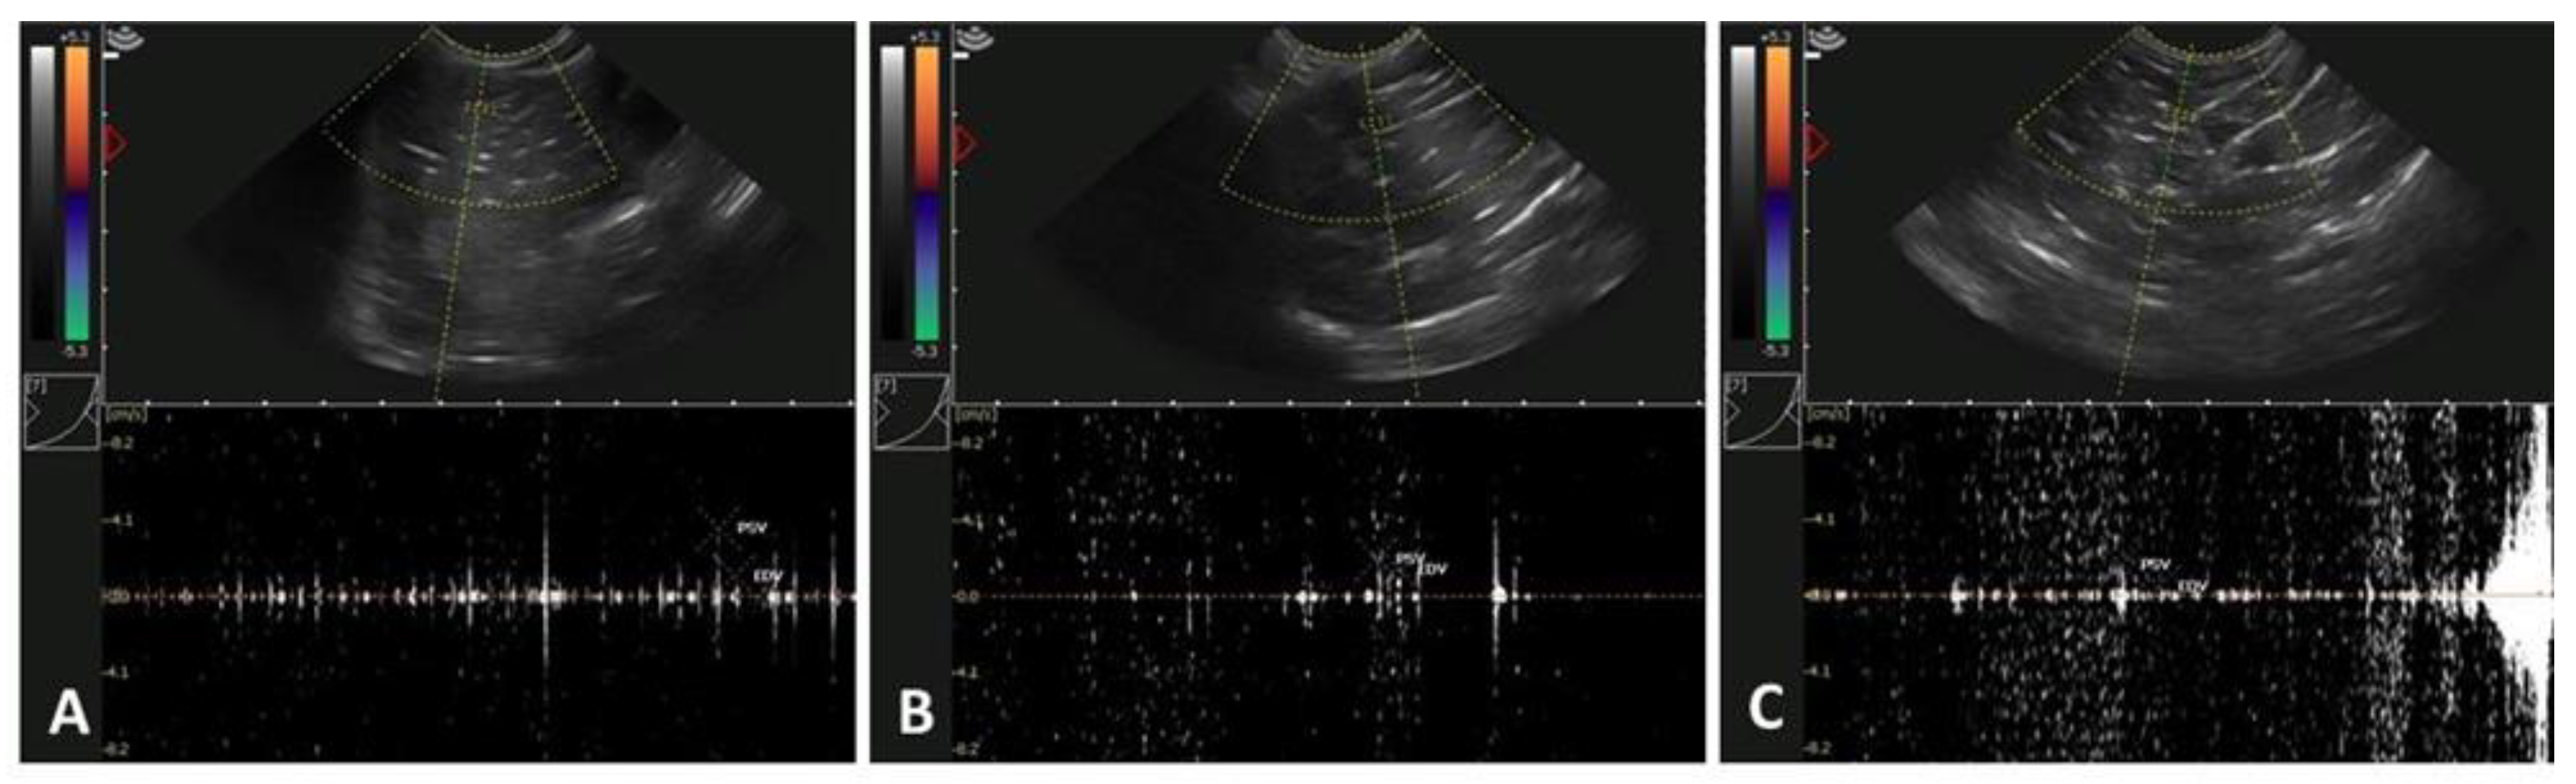

3.2. Age-Related Effects on Testicular Circulatory Dynamics in Alpacas

| Experimental Groups | n | Resistive Index (RI) | Pulsatility Index (PI) | Test. Vascular Area (% TVA) |

|---|---|---|---|---|

| YM (~12–14 mo.) | 5 | 0.54 ± 0.03 | 0.53 ± 0.08 | 9.16 ± 4.83 |

| IM (~24 mo.) | 5 | 0.49 ± 0.06 | 0.31 ± 0.09 | 3.77 ± 0.75 |

| OM (≥36 mo.) | 5 | 0.57 ± 0.05 | 0.47 ± 013 | 3.84 ± 0.25 |